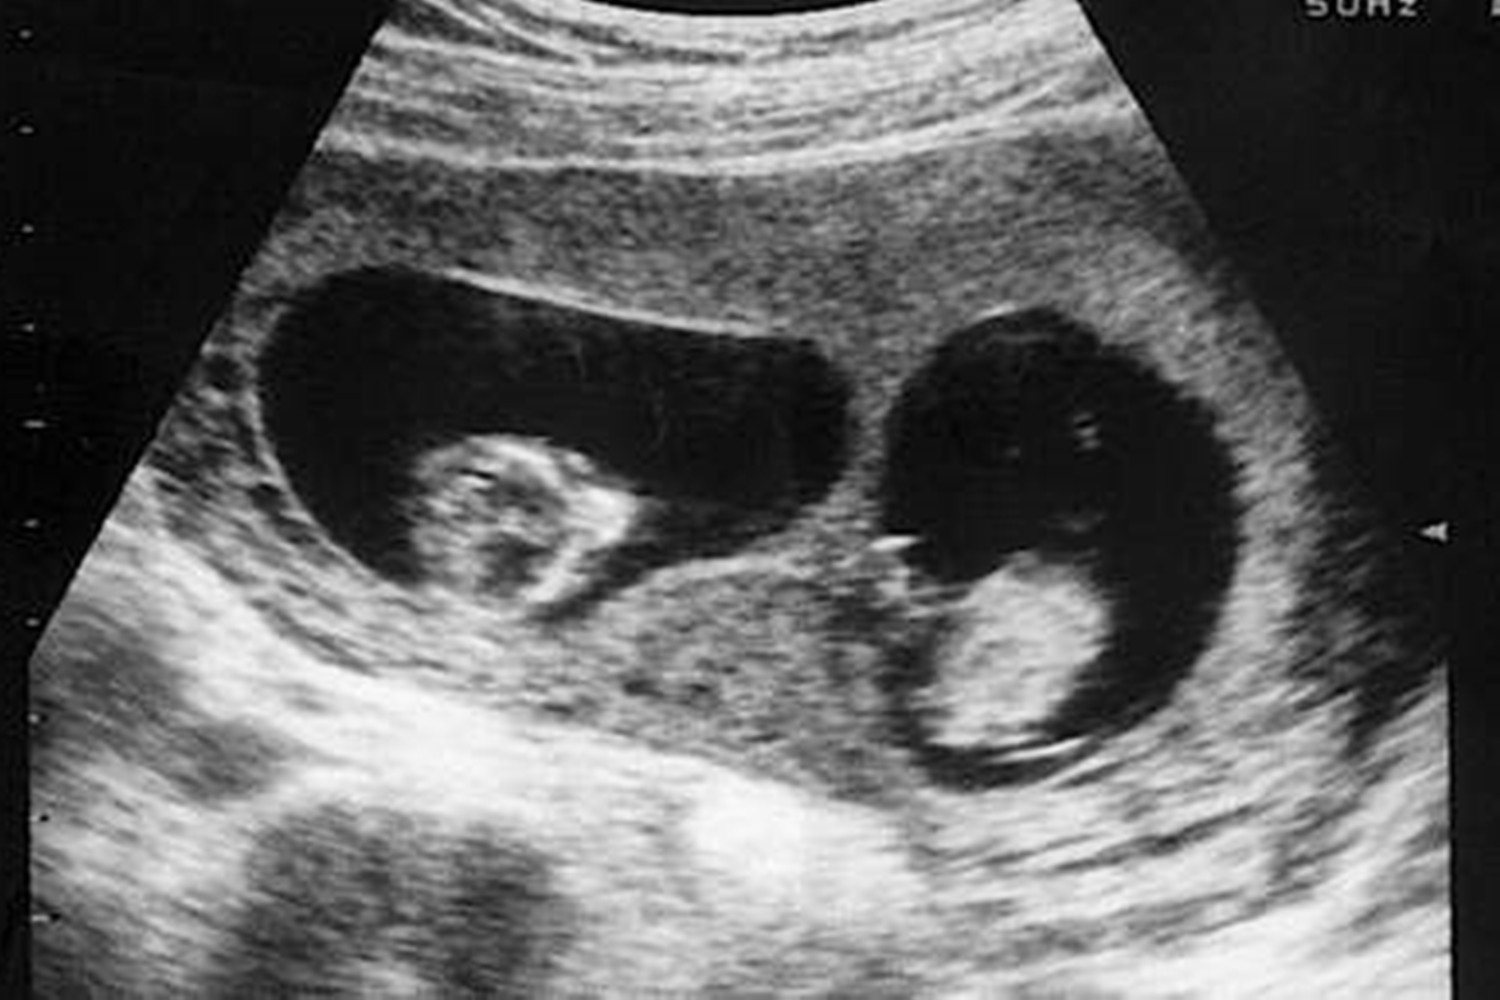

这块胎记有什么值得称奇的呢?原因在于其形状,与新生儿的龙凤胎姐姐孕期拍下的B超影像高度相似,下面跟大家说说细节。

龙凤胎姐姐腹中被“吸收”,将B超影像留在弟弟腿上

但事情没过多久就迎来了转折,之后做产检时,吉文斯查看B超影像发现两个胎儿的发育相差很大,姐姐弱弟弟强。

到了怀孕第13周,检查后医生称,超声影像显示腹中只存在一个胎儿了,另一个已死去并被吸收。

好在最后龙凤胎中的弟弟健康降生了,更令她惊喜的是,当护士抱着孩子到她跟前时,还特地指了这块腰果状胎记给她看,形状和被“吸收”的姐姐的B超影像十分相似。

吉文斯既惊讶,又感觉得到了慰藉,心想这可能是未出生的姐姐给弟弟留下的一种特殊回忆吧。